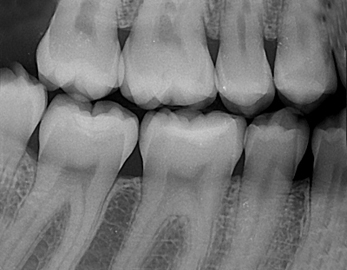

Retrokoronarni snimak je takodje dentalni radiogram koji se koristi za dijagnostiku karijesa i procenu stanja parodoncijuma izmedju zuba. Na njemu se vide krunice gornjih i donjih zuba, medjuzubni prostori u bočnoj regiji i rade se kao kontrolni snimci pri periodičnim kontrolnim pregledima.